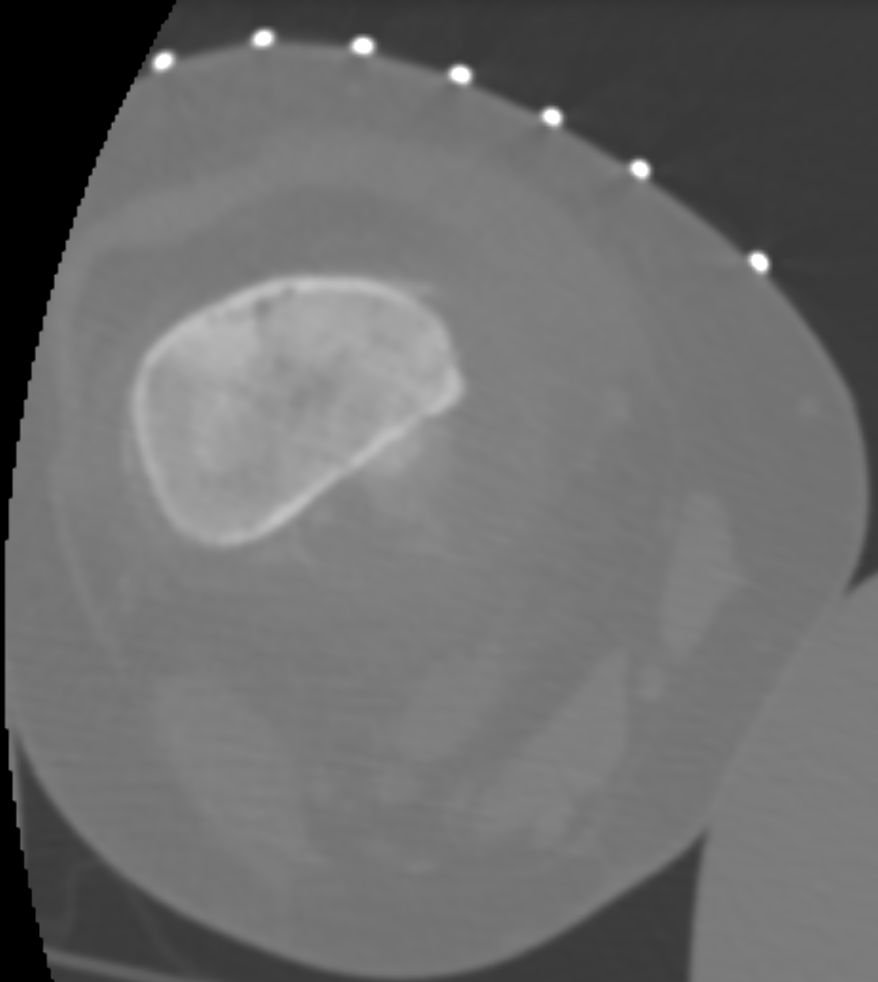

IGTFusion used to guide and confirm accurate biopsy needle placement in soft tissue mass adjacent to femoral bone tumor that was not visible on CT during the procedure, but was visible on the pre-treatment MRI.

- Registered a pre-procedure MRI with procedural CT

- Fusion adjusts for rotation of femur between images due to leg positioning

- Saved procedure time by identifying the occult soft tissue mass for biopsy